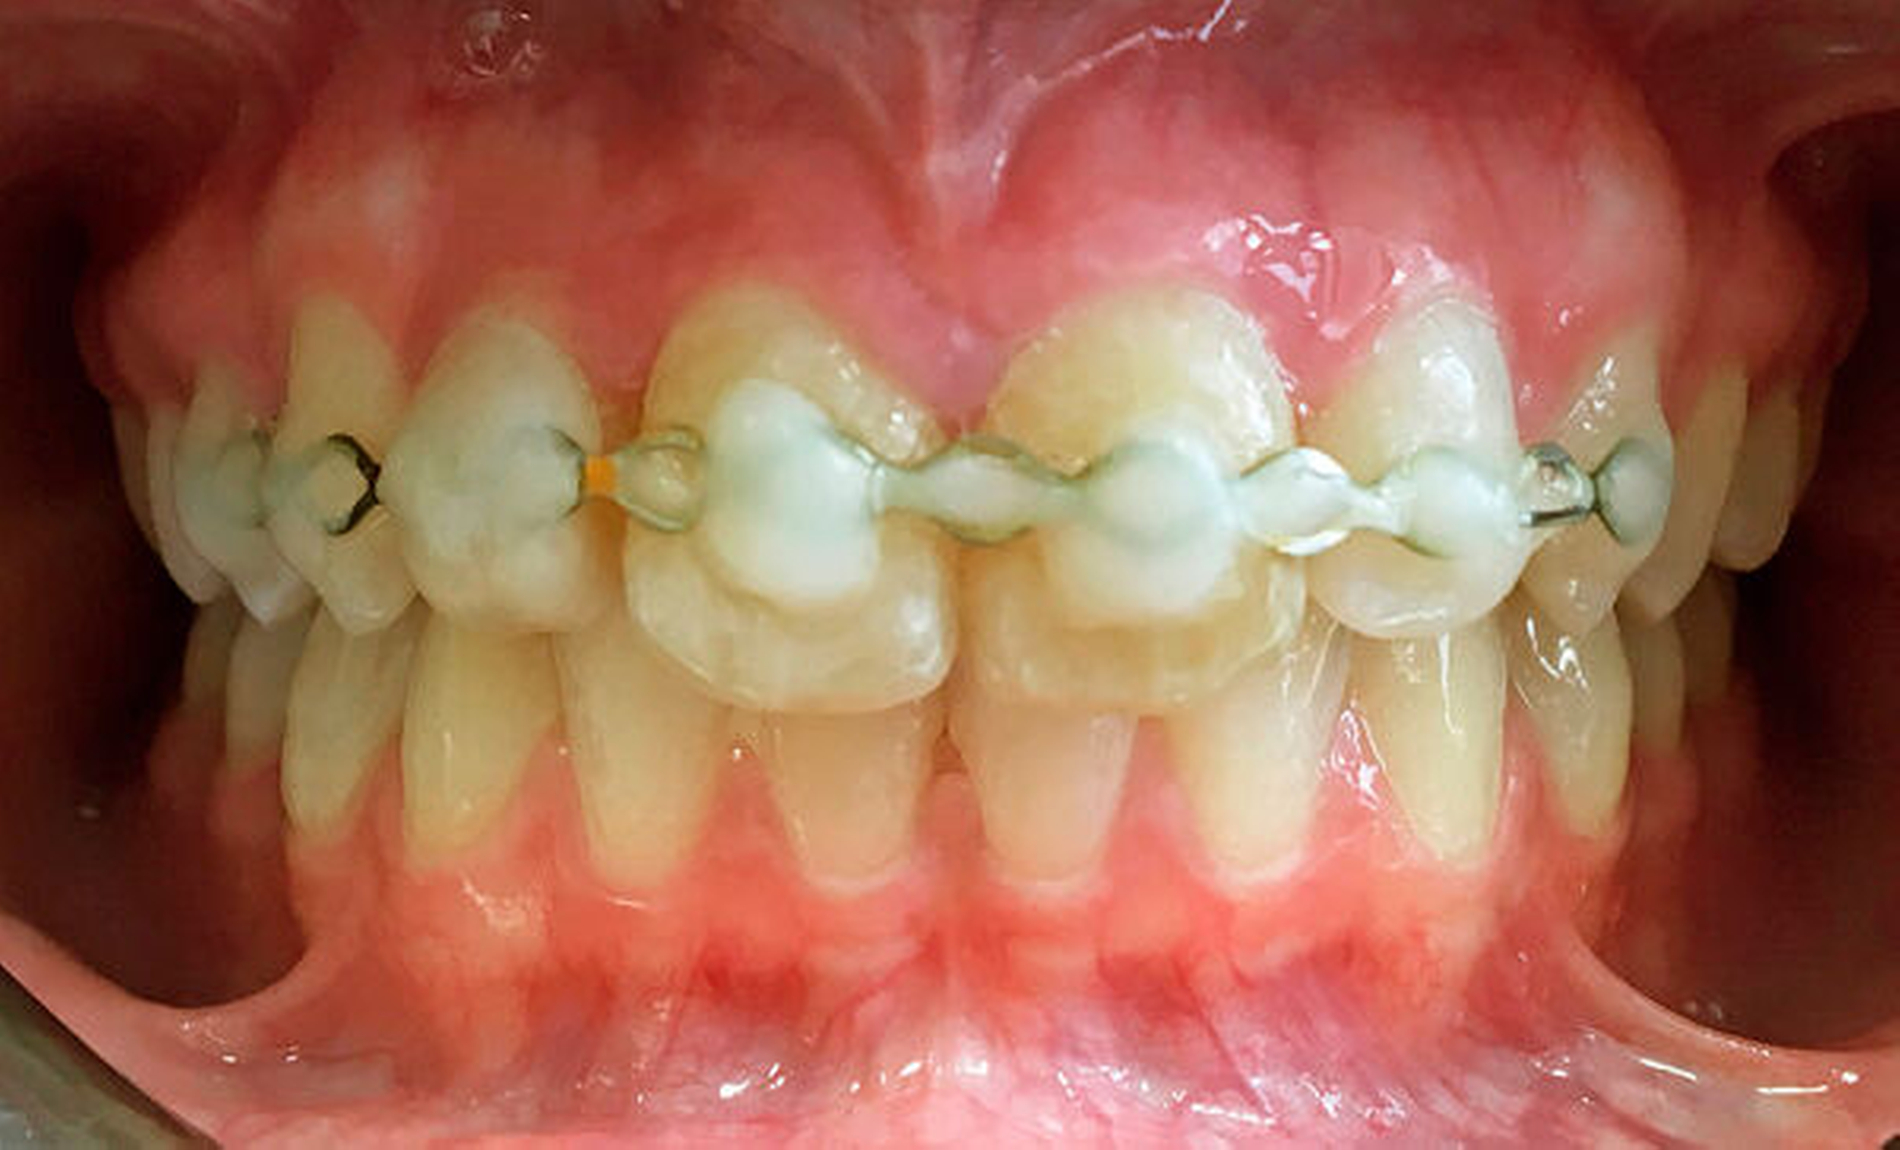

In Lokalanästhesie wurde dann die Replantation der Zähne 12, 11 und 21 in die weitgehend intakten Alveolen vorgenommen. Es folgte die Fixierung der Zähne regio 14–23 mittels Titantraumasplint (TTS) und Komposite. Das postoperative OPTG zeigt ein regelrechtes Repositionsergebnis der Zähne (Abbildung 5).

Die Antibiose sollte oral bis zum siebten postoperativen Tag fortgeführt werden. Weiterhin wurde weiche Kost für zwei Wochen empfohlen, die Mundhygiene sollte regulär fortgesetzt werden. Zur klinischen Verlaufskontrolle erfolgte nach 14 Tagen eine ambulante Vorstellung in unserem MVZ für Mund-, Kiefer- und Gesichtschirurgie. Die Wundheilung verlief regelrecht und die replantierten Zähne wiesen unter Schienung einen Lockerungsgrad von 0 auf. Eine Perkussionsempfindlichkeit lag nicht vor. Die Okklusion war subjektiv analog dem Zustand vor dem Unfall. Nach knapp vier Wochen Schienung löste sich der Kompositverbund zu Zahn 12. Der Zahn hatte klinisch einen Lockerungsgrad von 2, daher wurde er erneut adhäsiv an der vorhandenen TTS fixiert (Abbildung 6).

In der fünften postoperativen Woche konnte die dentale Schienung durch den Hauszahnarzt entfernt werden und die replantierten Zähne wiesen keinen Lockerungsgrad auf. Nach zehn Wochen war die Patientin unverändert beschwerdefrei, wobei sie ein minimales Zahnlockerungsgefühl an 11 angab. Klinisch war dies allerdings nicht zu verifizieren. Auch die Gingiva zeigte klinisch einen regelrechten Befund (Abbildung 7).